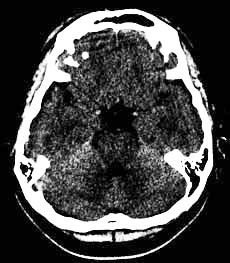

頭部CT

X線を使用する撮影ですが、細いX線ビームを回転しながら出してそれをコンピュータ画像処理したものです。

スライス番号は、すぐ下のCT画像に対応しています。上段の図をクリックすると下段のCT画像が拡大して見られます。